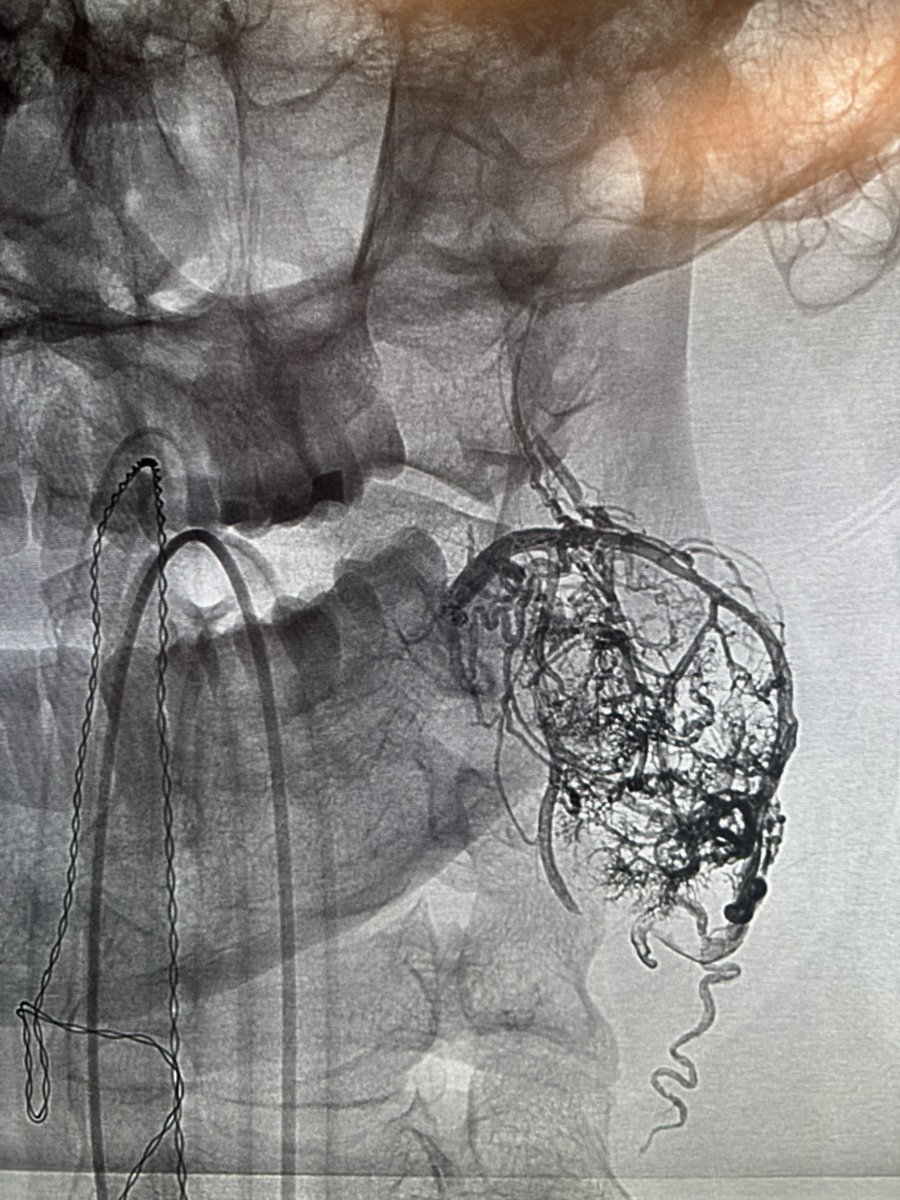

New multicenter study: The RED 43 catheter is safe and effective for aspiration thrombectomy in distal medium vessel occlusions. High recanalization (83–87%) & low symptomatic ICH (1%) rates. 🧠 Read more: jnis.bmj.com/content/early/… #Stroke #NeuroIR #RED43